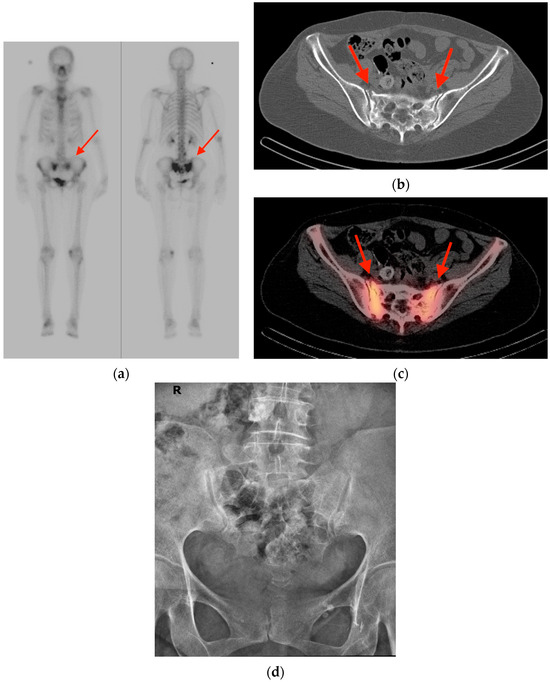

2.5. Vertebral Hemangioma

- Gerard, P.S.; Wilck, E. Spinal hemangioma. An unusual photopenic presentation on bone scan. Spine 1992, 17, 607–610. [Google Scholar] [CrossRef]

- Domínguez, M.L.; Rayo, J.I.; Serrano, J.; Sánchez, R.; Infante, J.R.; García, L.; Durán, C. Vertebral hemangioma: Cold vertebrae on bone scintigraphy and fluordeoxy-glucose positron emission tomography-computed tomography. Indian J. Nucl. Med. 2011, 26, 49–51. [Google Scholar] [CrossRef]

- Solav, S.V.; Savale, S.V.; Patil, A.M. False-positive FDG PET CT Scan in Vertebral Hemangioma. Asia Ocean. J. Nucl. Med. Biol. 2019, 7, 95–98. [Google Scholar] [CrossRef]